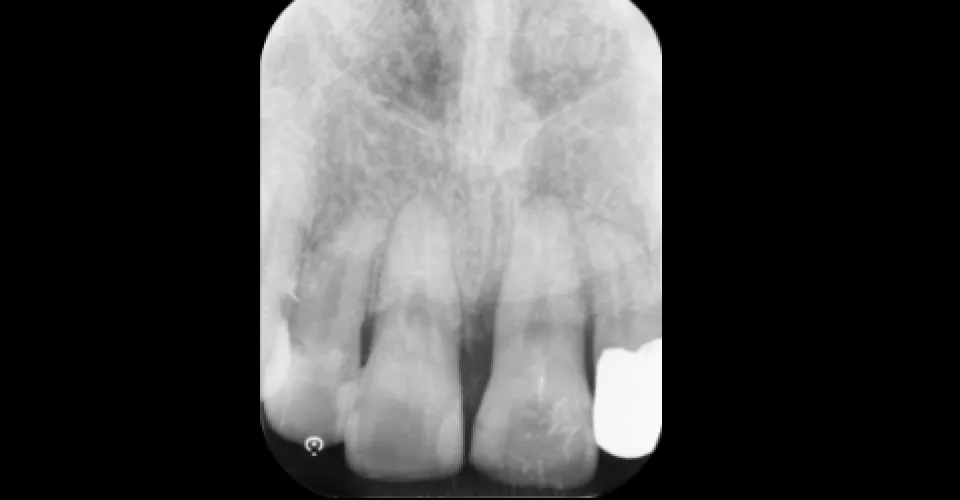

精密検査による「保存判定」

「抜歯」という診断を下す前に、検証すべきことがあります。

従来の2次元レントゲンでは、重なり合った根の形や、裏側に隠れた病巣の広がりを正確に把握することはできませんでした。

LOTUS DENTAL CLINIC 東京(ロータスデンタルクリニック東京)の治療体制

-

歯科用CT

(三次元画像解析)根の数、湾曲度、病巣の大きさ、骨の溶け具合を3Dで立体的に解析します。難治性の原因がどこにあるのかを特定し、治療の攻略ルートを設計します。

「診断」の精度が、歯の寿命を決定づけます。根管治療の成否は、実際に手を動かす前の「診査・診断」で9割が決まると言っても過言ではありません。 当院では、初診ですぐに削るようなことはいたしません。まずは患者様のお話を丁寧に伺い、歯科用CT(三次元断層撮影)を用いて、従来のレントゲンでは見えない複雑な根管形態や病巣の広がりを立体的に把握します。さらに、マイクロスコープ(歯科用顕微鏡)で歯の微細な亀裂(マイクロクラック)まで確認し、無駄な治療を回避するとともに、最短ルートでの治癒を目指す治療計画を東京都の極限まで歯を残す精密根管治療を行う当院では立案しています。

医科用CTの約1/10~1/100程度であり、身体への影響は極めて少ないです。 当院で導入している歯科用CT(コーンビームCT)は、非常に低被曝で撮影が可能です。 根管治療において、複雑な根の形態や病巣の広がりを三次元(3D)で正確に把握することは、治療の成功率を飛躍的に高めるために不可欠です。被曝によるわずかなリスクよりも、正確な診断なしに治療を行うリスクの方が遥かに大きいと私たちは考えています。